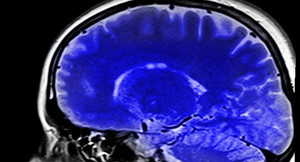

Công nghệ 17/8: Chip não giải mã suy nghĩ con người với độ chính xác 74%

Một thiết bị cấy ghép não đang được phát triển có thể chuyển đổi suy nghĩ thành văn bản, mở ra hy vọng giao tiếp cho người mất khả năng nói.

Tỷ phú Elon Musk cho biết lần đầu tiên Neuralink đã cấy ghép chip não của họ vào một bệnh nhân với "kết quả đầy hứa hẹn".

Việc truyền đạt suy nghĩ mà không sử dụng ngôn từ nghe giống như trong một bộ phim viễn tưởng nhưng có thể sẽ sớm trở thành hiện thực.